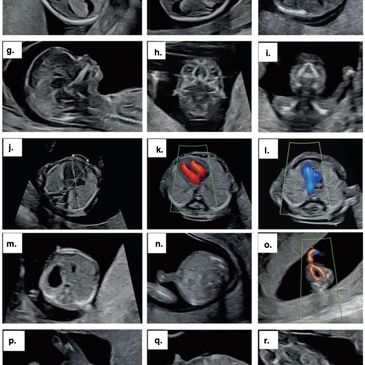

🇺🇸Fetal morphology ultrasound is one of the most important examinations during pregnancy.

At Ultra Medical Clinic, we provide detailed fetal morphology in Prishtina using advanced ultrasound technology to carefully assess your baby’s development. It is done by MSc. Dr. Mirlinde Daci sonologist USA APCA certified No. 203686.

Fetal morphology is a detailed ultrasound scan that evaluates the baby’s anatomy and development.

It examines:

This scan helps ensure that the pregnancy is progressing normally.

Fetal morphology is typically performed between:

➡️ 20 – 24 weeks of pregnancy

This timing allows for the most accurate evaluation of fetal structures.

This examination helps:

Early evaluation allows for better planning and care when needed.

At Ultra Medical Clinic, fetal morphology is performed using modern high-resolution ultrasound systems that allow:

This supports confident evaluation and monitoring.

Fetal morphology requires experience and precision.

Our focus includes:

Every scan is performed in a professional and supportive setting.

The fetal morphology scan is:

The examination usually takes longer than routine scans because of the detailed assessment involved.

If you are looking for detailed fetal morphology in Prishtina, Ultra Medical Clinic provides advanced pregnancy ultrasound focused on accuracy and reassurance.